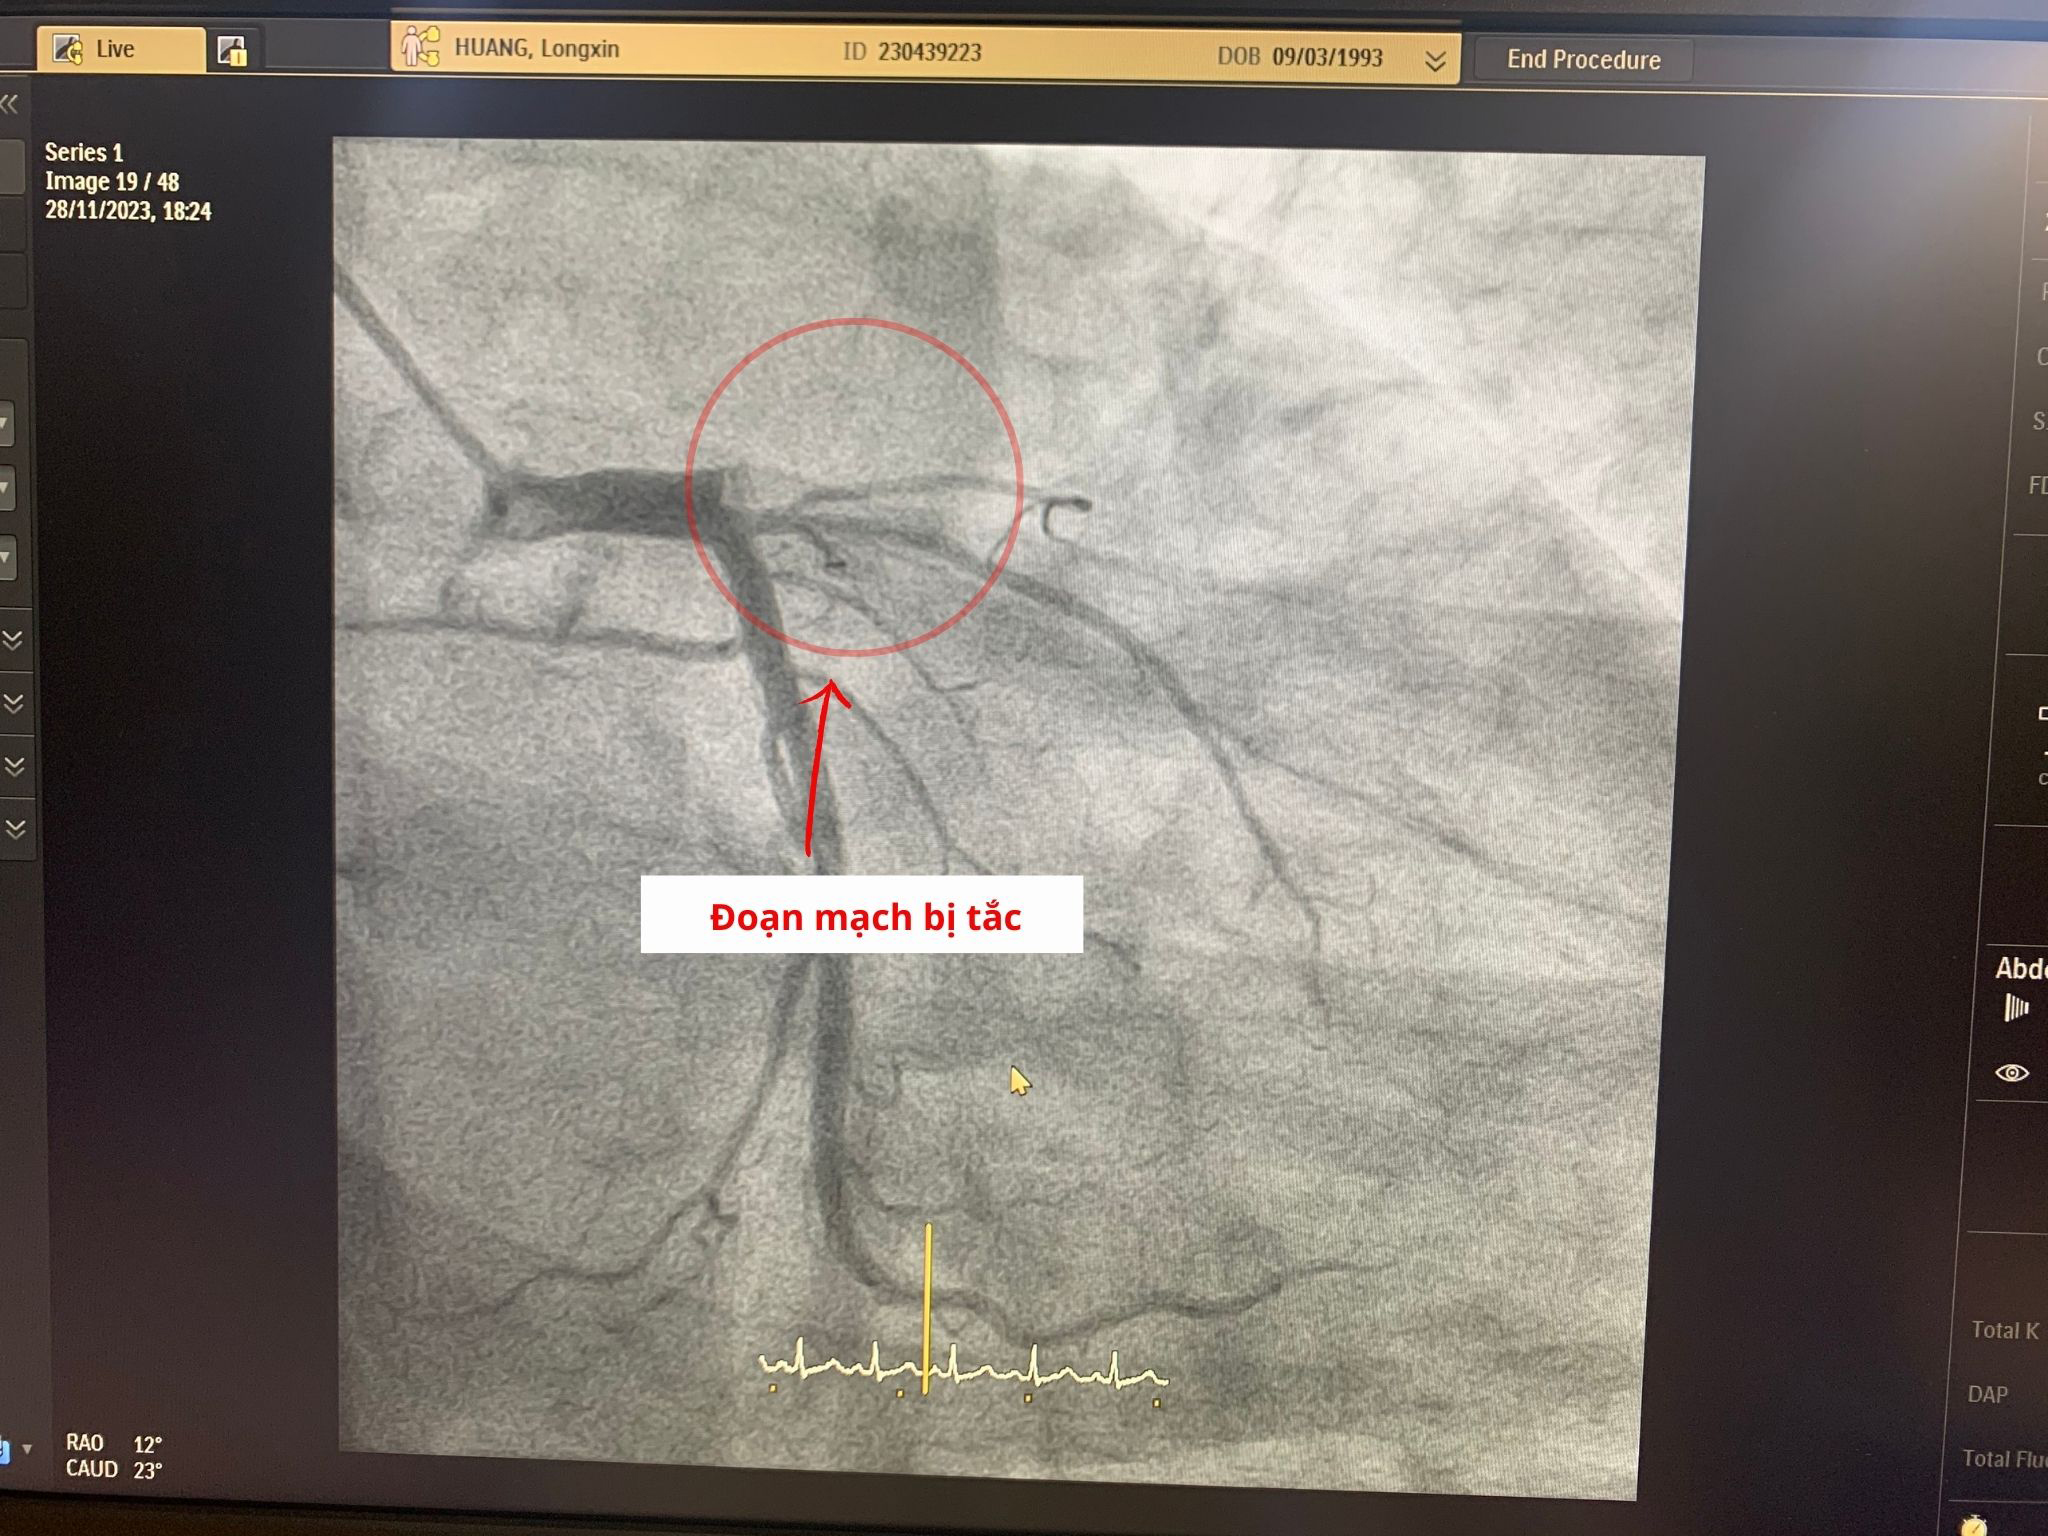

Qua thăm khám ban đầu, bác sĩ chẩn đoán bệnh nhân bị nhồi máu cơ tim cấp. Ngay lập tức, bệnh nhân được chuyển lên phòng can thiệp để chụp mạch vành số hóa xóa nền DSA. Kết quả ghi nhận, bệnh nhân bị tắc hoàn toàn ngay từ lỗ vào động mạch liên thất trước do huyết khối và hẹp nặng từ trước đó, nguy cơ đột tử rất cao.

Đoạn mạch bị tắc hoàn toàn ngay từ lỗ vào động mạch liên thất trước